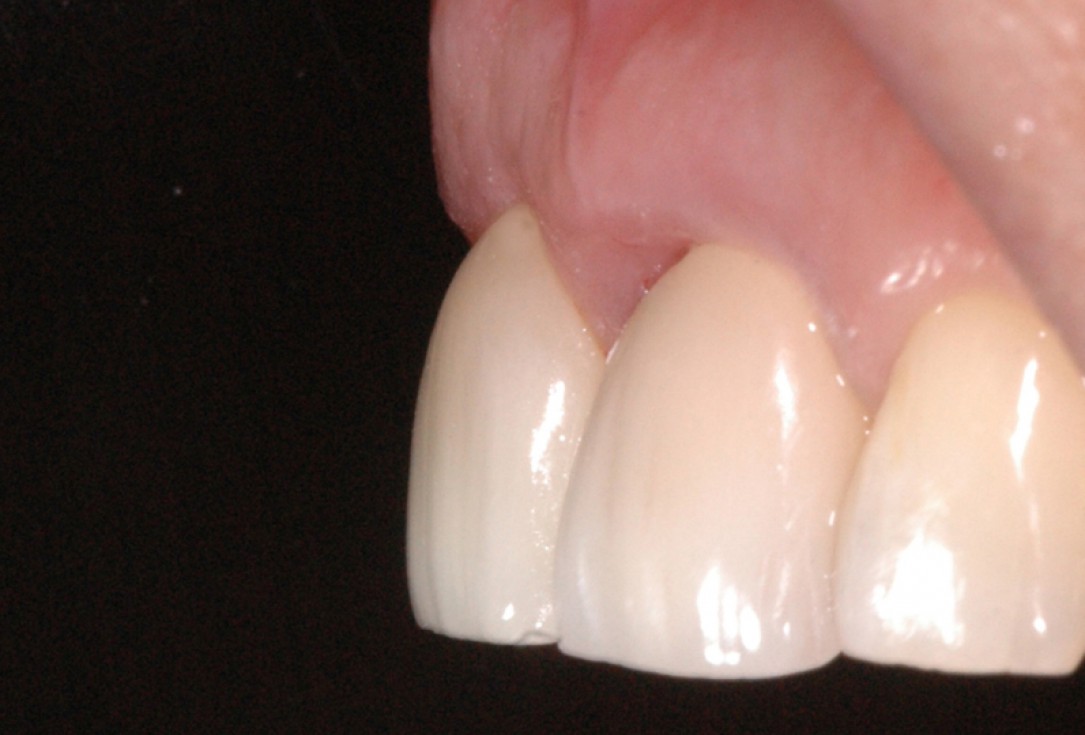

16/18 - Final restoration 15 months after implantation and stability of root coverage in regio 23GBR together with soft tissue augmentation with mucoderm® and maxresorb® - Dr. S. Scherg